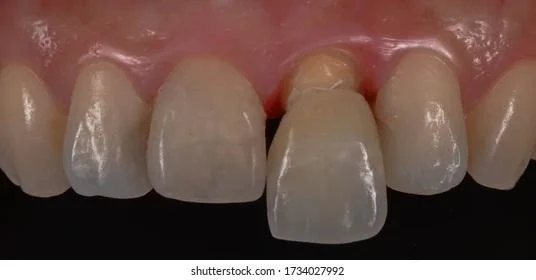

Step 3: Scanning periodontal tissue, occlusion, and implant position to fabricate customized abutment and crown.

Scanning is performed after the implant has integrated and stabilized, usually 2 months after implant placement.

Unlike traditional implant methods that use manual impressions, personalized implants use scanning technology for impression taking. This technology not only accurately records the implant position but also precisely captures the morphology and structure of periodontal tissues and the patient’s occlusion to transfer into virtual design software.

Step 4: Placement of the customized abutment and fixation of the ceramic crown.

After scanning, the data is sent to the design center for simulation. The customized abutment is manufactured there and then placed intraorally. The abutment is designed to fit precisely with the periodontal tissue structure.

Step 4: Scanning the implant position, periodontal tissue, and occlusion.

After the implant has integrated and stabilized (2–4 months), the patient returns to the clinic where scanning technology is used to capture the entire oral structure.

It should be noted that manual impression methods are not considered personalized implant solutions because they cannot accurately copy not only the teeth but also periodontal tissues, occlusion, and implant position. Therefore scanning technology is mandatory.

Step 5: Design of the customized abutment and ceramic crown.

The scanning data are again imported into Exocad. Combined with pre-treatment anthropometric data, a customized abutment and ceramic crown are designed based on ideal periodontal tissues, facial features, and dental arch of each individual, ensuring harmony in aesthetics, occlusion, and periodontal biology.